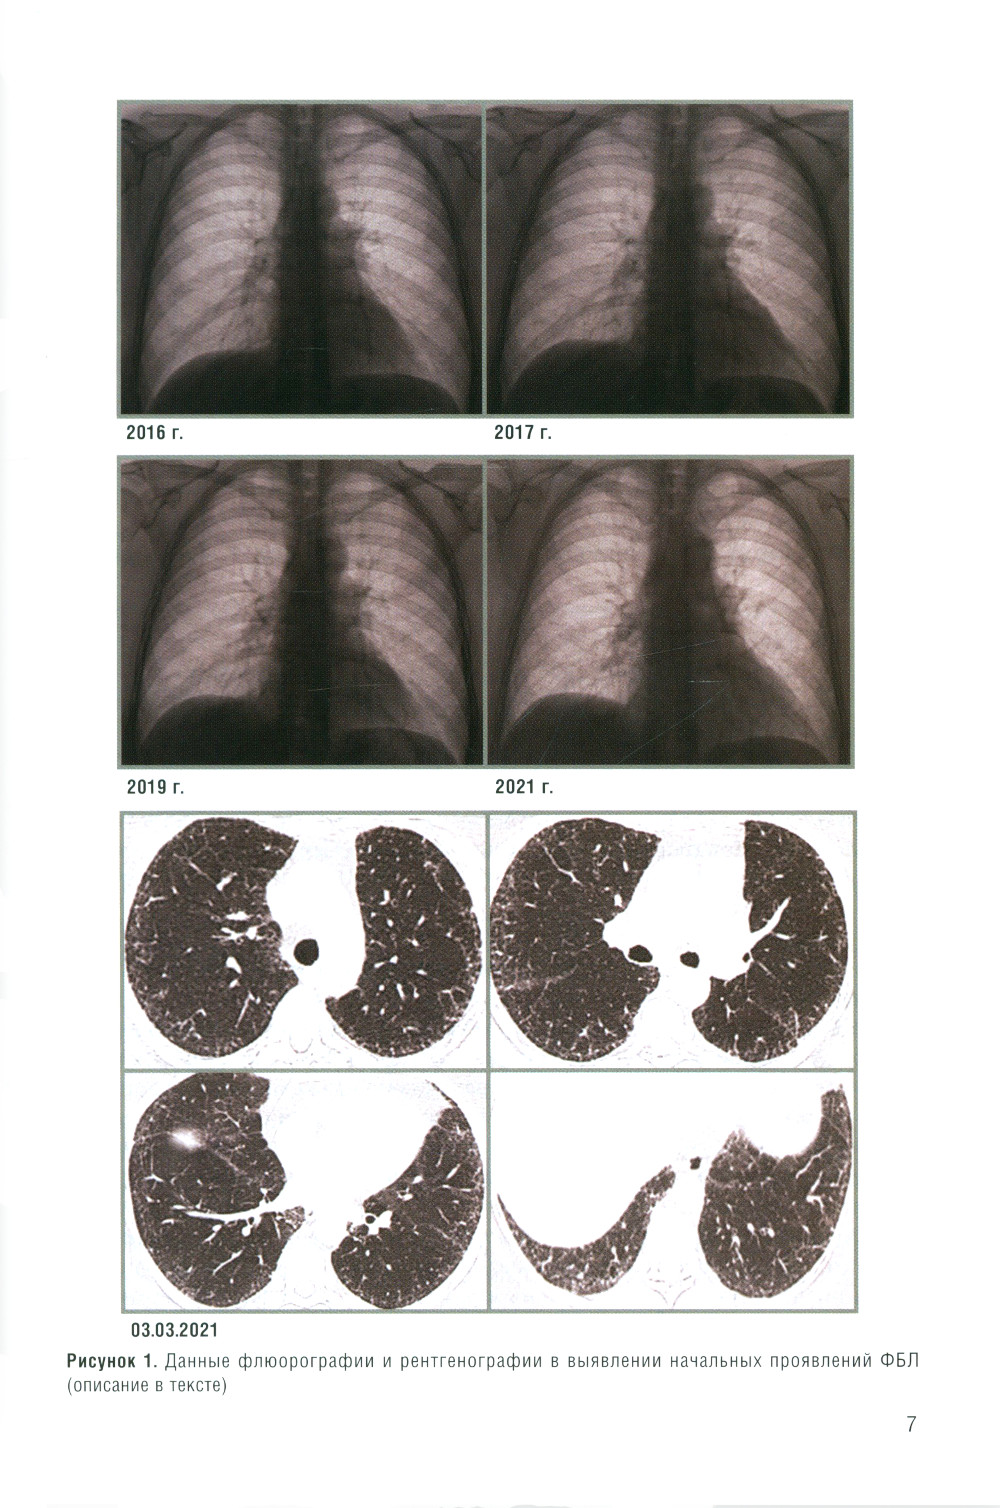

В книге рассматриваются лучевые проявления различных вариантов фиброзирующих болезней легких с позиции рентгенолога, принимающего участие в работе мультидисциплинарного консилиума. Автор выражает слова благодарности директору института НИИ интерстициальных и орфанных заболеваний легких д.м.н., профессору М.М. Ильковичу и его коллективу за возможность участвовать в этих разборах, где рентгенолог видит все сложности анализа клинических проявлений, лучевой и дифференциальной диагностики ФБЛ. В книге приведены примеры реальной работы рентгенолога (с некачественным лучевым архивом, сменой морфологических заключений, свидетельствующие о важности правильного лучевого алгоритма и методичности анализа лучевых исследований). Также приведены примеры нозологических заключений рентгенолога, без которых трактовка заболевания уходит в другую сторону и ухудшает его течение без своевременно начатого лечения.| Издательство | Элби |